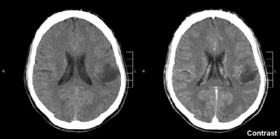

Магнітно-резонансная томографія, МСКТ комп’ютерна томографія, ангіографія мозкових судин з контрастом, сцинтиграфія призначаються для уточнення локалізації процесу.